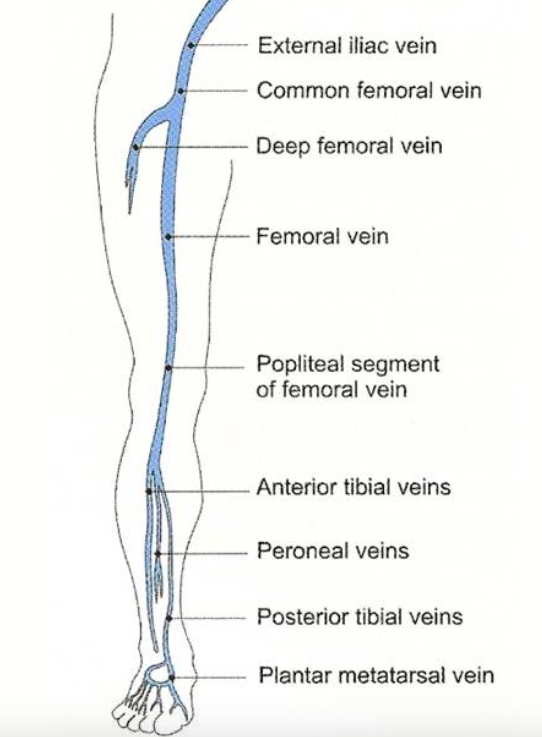

venous anatomy thrombosis superficial veins deep health sources trusted

venous dvt deep thrombosis lower extremity system evlt

deep vein veins thrombosis leg

extremity venous thrombosis